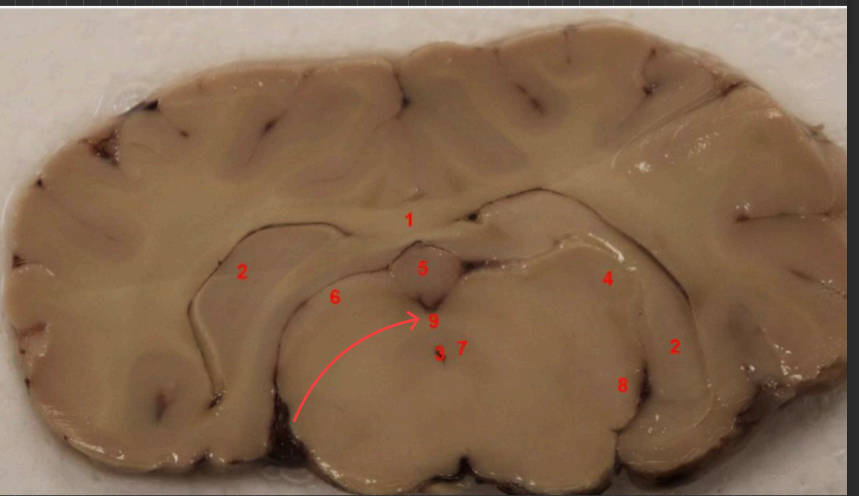

what area is this

mamillary bodies

what tract is this

hippocampal commissure

what area is this?

Denate Gyrus

what is this

Habenula

fornix

mammillothalmic tract

hippocampus

entorhinal cortex

subiculum

lateral geniculate nucleus, filters visual signals, mediates attention by prioritizing important information,

what is this (13)

hippocampal commisure

LGN

enthorinal cortex

MGN

thalamus